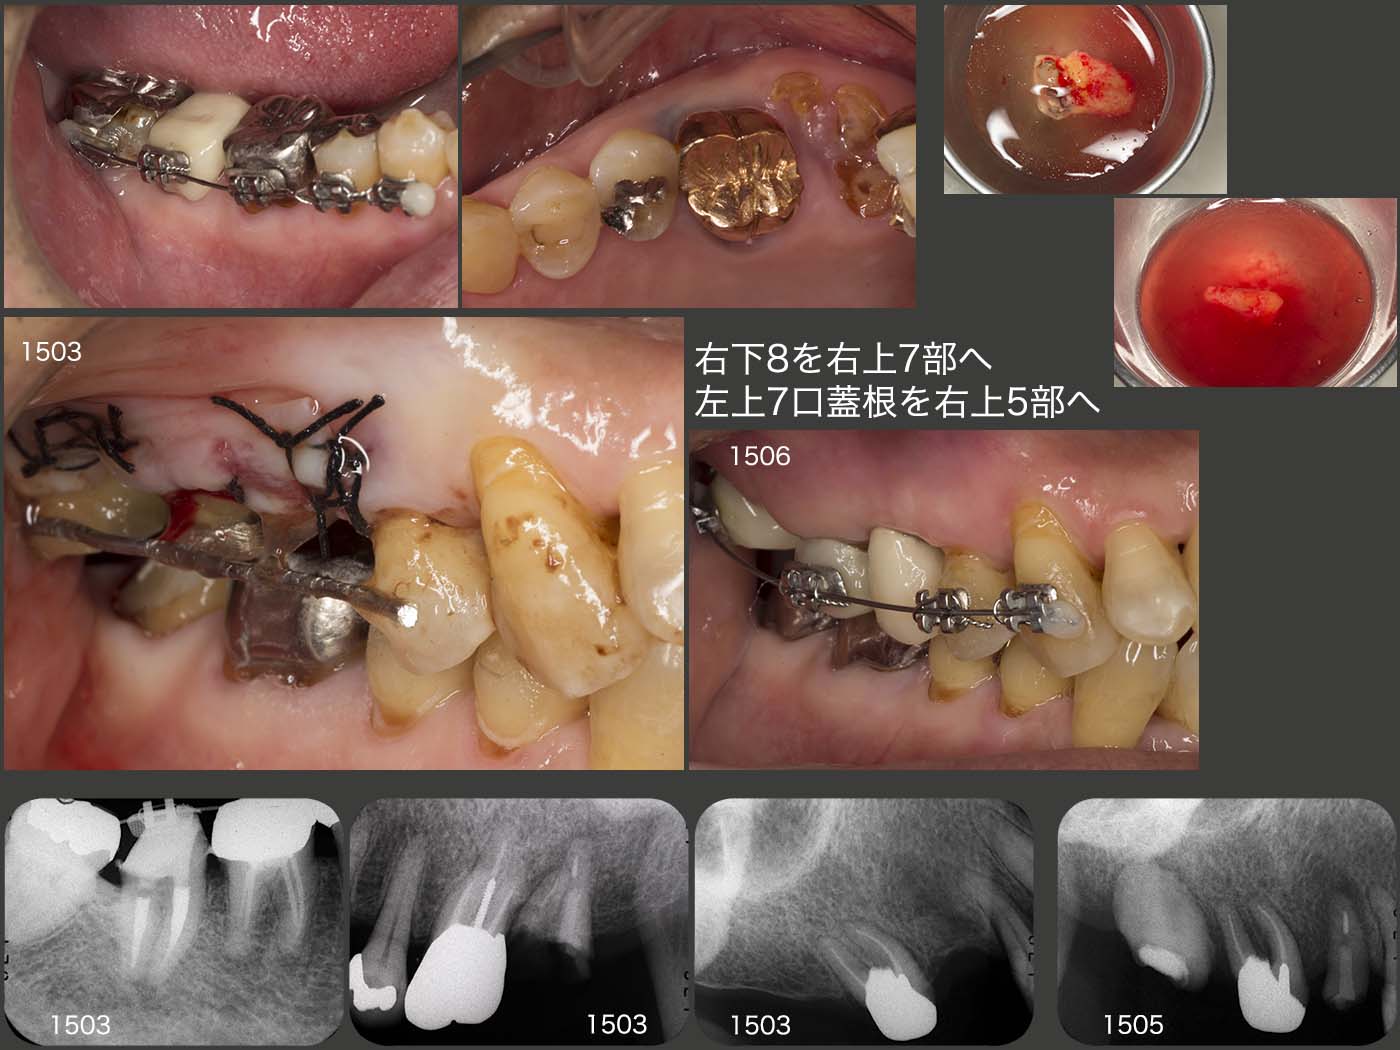

最終的には右側の咬合支持を増すために,右下8を右上7部に,左上7の口蓋根を右上5部へ移植することにした.なお右下8に挻出力を加え,歯根膜を傷つけずに抜歯しやすいように工夫した.2015年3月に移植を行った.なお,移植された右上7が咬合平面より大分低位に位置してしまったため,6月5日に矯正的挻出を施し,7月22日に終了した.

移植の術前,術後と患者さんは左側咬みを余儀なくされたため,2015年8月,左側の咬合支持歯である,左下5に歯根破折が生じてしまった.そこで左下7にコーヌス冠,健全歯である左下4にはクラスプを用いた義歯を製作した.